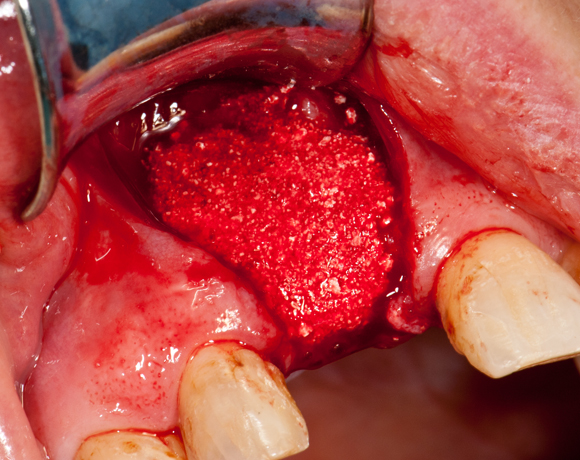

Bild 10: Eingebrachtes CEROS® TCP PUTTY